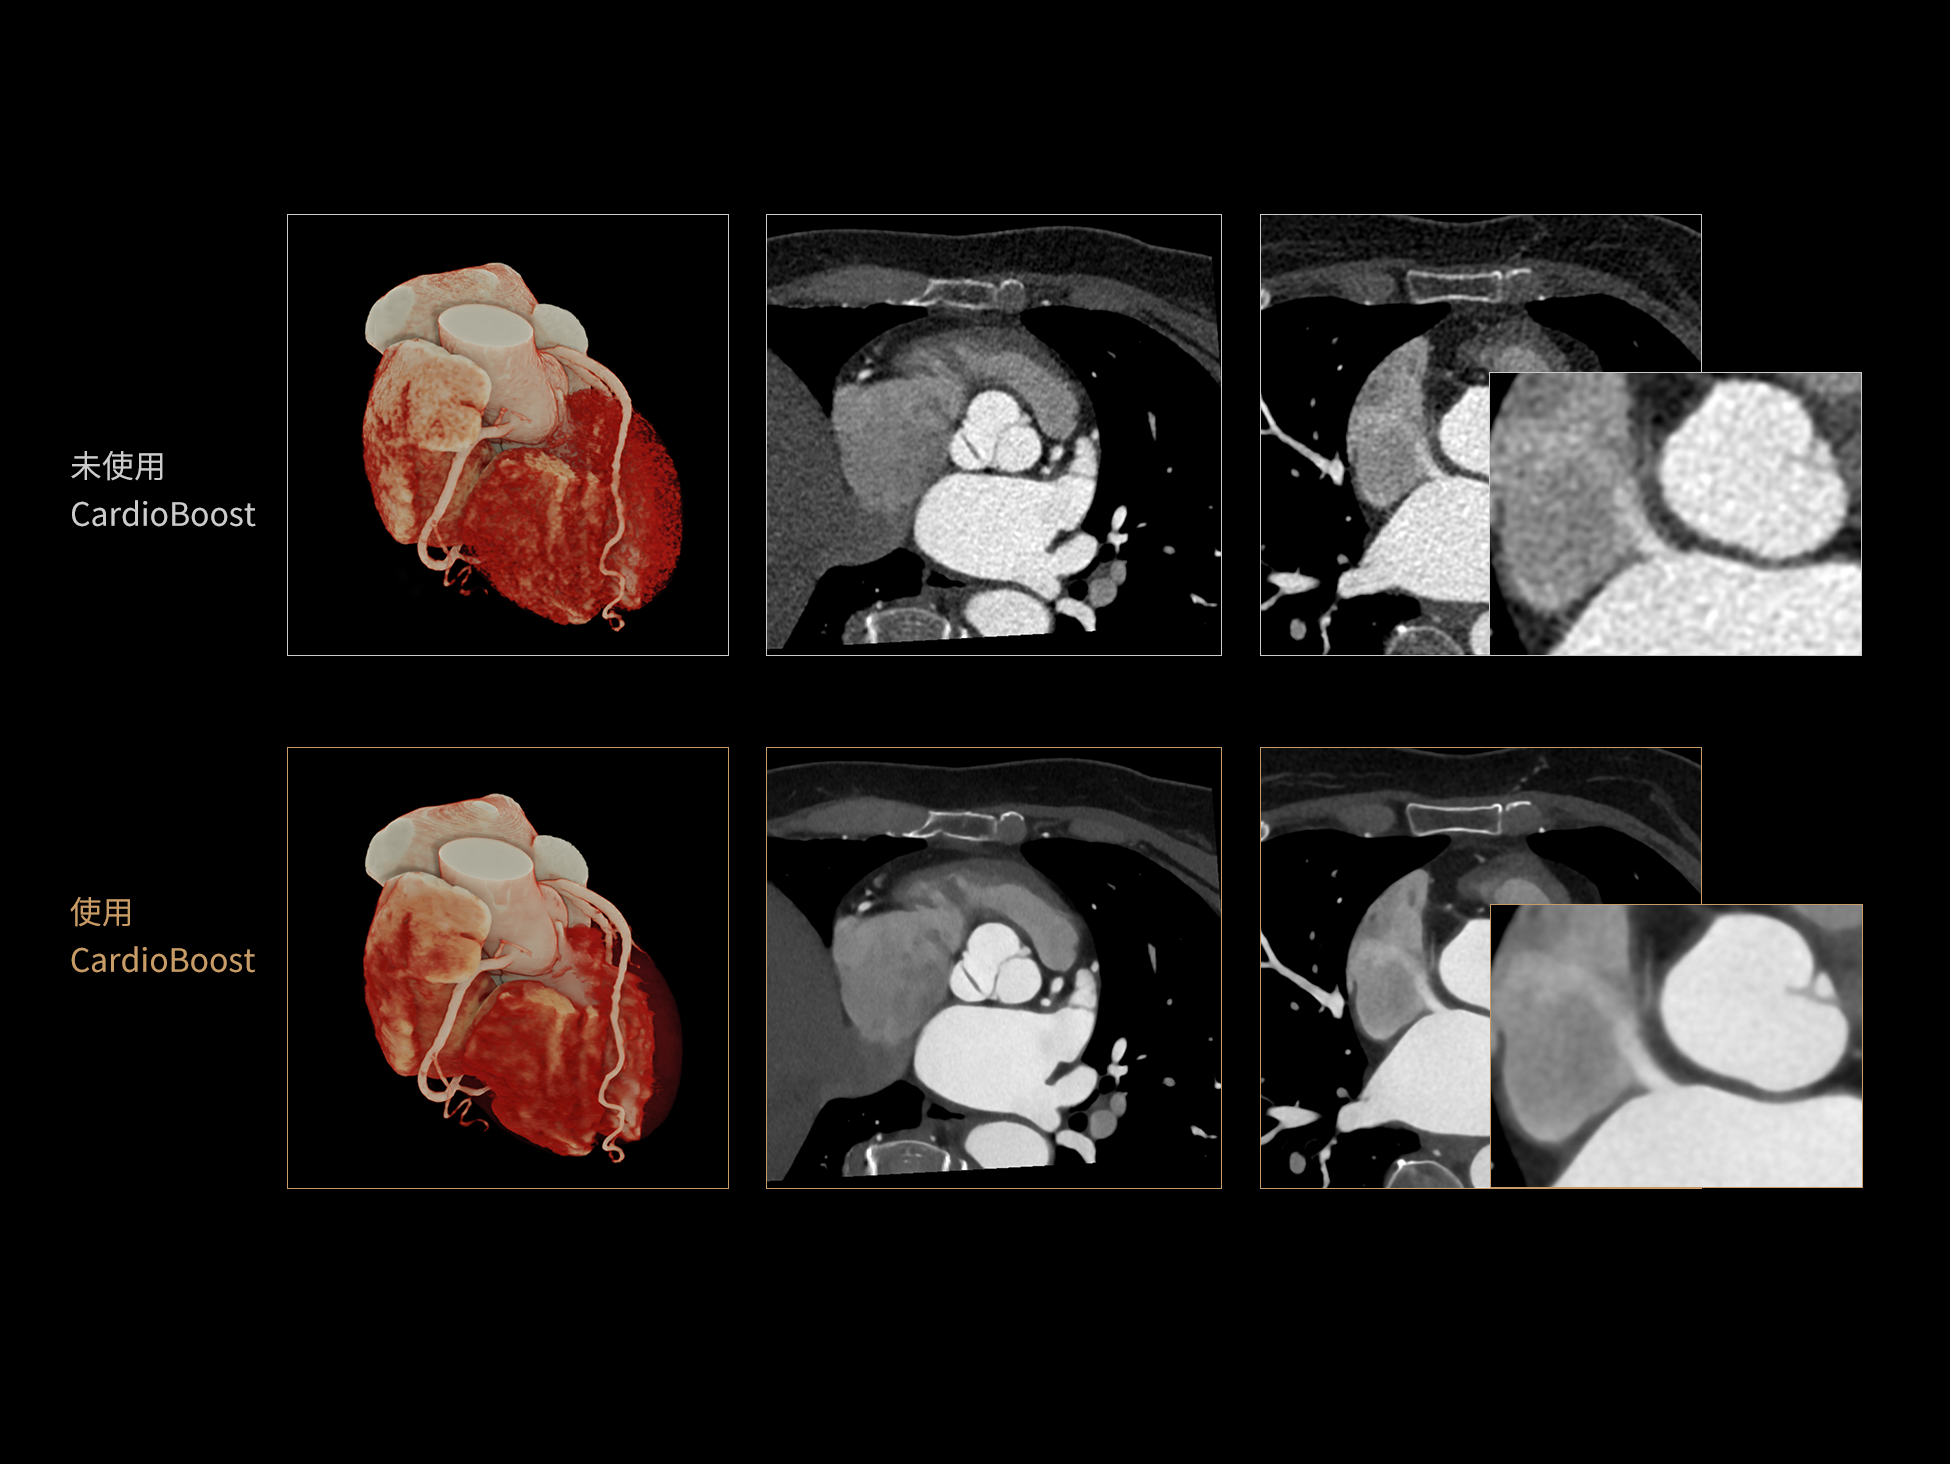

CardioBoost:专属网络设计,重塑心脏影像表现

目前心脏的 CT 检查还存在辐射剂量偏高、空间分辨率不足、 致密钙化伪影影响冠脉狭窄程度评估等方面的限 制[1][2]。CardioBoost 技术专为心脏 CT 高清成像而开发,通过 3D 神经网络的深度学习技术,利用先进的注意力机制在识别关键成像特征方面的出色表现,能够精确地聚焦于斑块、支架以及微小血管等关键细节,清晰展示这些结构与冠脉血管的边界,从而显著提高诊断的准确性,并提升医生的诊断信心。创新的 CardioBoost 心脏图像重建算法,不仅实现了图像清晰度的提升和伪影的去除,更能在减少辐射剂量的同时,保证心脏图像的高质量和图像纹理的自然。

CardioBoost核心创新

采用 3D 神经网络的空间结构优势与精细的组织分类能力,CardioBoost 技术优化了组织对比,高清展示血管斑块,使斑块与血管边缘的轮廓清晰可辨,提升斑块诊断与评估的精确性。

借助 3D 神经网络设计、空间注意力机制聚焦与特征强化作用,CardioBoost技术提升图像的空间分辨率,实现冠脉支架的高清成像,对支架形态与管腔通畅度的评估更精准。

CardioBoost 整合先进的 3D 神经网络和空间注意力机制,大幅增强数据处理的速度与精确度。该技术能有效抑制由致密钙化引起的晕状伪影,清晰展现钙化斑块的原始结构和大小,对冠脉狭窄的评估更加精确可靠。

对比度强化模块

分辨率强化模块

伪影抑制模块